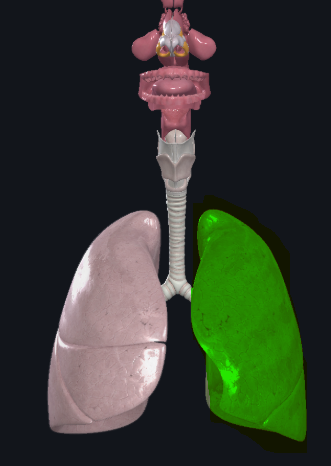

Superior lobe of the left lung

What structure is this?

Inferior lobe of the left lung

What structure is this?

Left lung

What structure is this?

Oblique fissure of left lung

What structure is this?